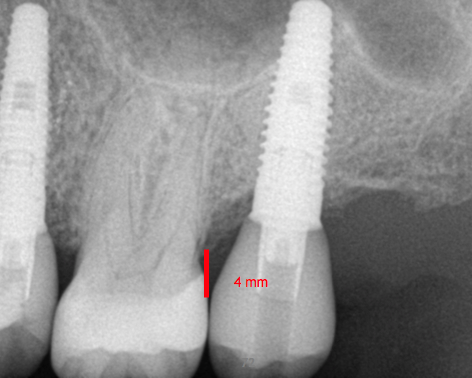

Fig 3. 3 to 4 mm is the distance apically from the restorative platform to the buccal-gingival margin.

Figure 3

The next set of numbers is "3-4," which represents how far apically the restorative platform should be from the buccal-gingival margin. Measuring down 4 mm from the buccal-gingival margin helps get the implant into the desired position (Figure 3). However, a range of 3 to 4 mm is given because the measurement may vary depending on the condition of the site. In the case of a completely healed site, the restorative platform should be just 3 mm below the gingiva. But in a circumstance of immediate placement, 4 mm is better because, on average, 1 mm of bone on the buccal crest of the extraction site may be lost. Another reason for the distance of 3 to 4 mm is to allow room to create the right type of contour so that gingival tissue can be supported and a natural-looking soft-tissue esthetic can be created. When measuring the apical distance between a restorative platform and the buccal-gingival margin, it is better to err on the side of going slightly too deep because if too shallow, it will be difficult to create the type of subgingival contour that will support the tissue well. In other words, it would be difficult to get good esthetics. A ridge lap over the gingival margin is not a good idea because it may create an area that is difficult to properly clean and thus runs the risk of developing peri-implant mucositis or peri-implantitis. The situation could then result in the recession and loss of bone and/or terrible esthetic results. Furthermore, because many mechanical variables are present in the oral cavity, the proper measurement between the implant and the bone is important for treatment planning and longevity of the implant.15